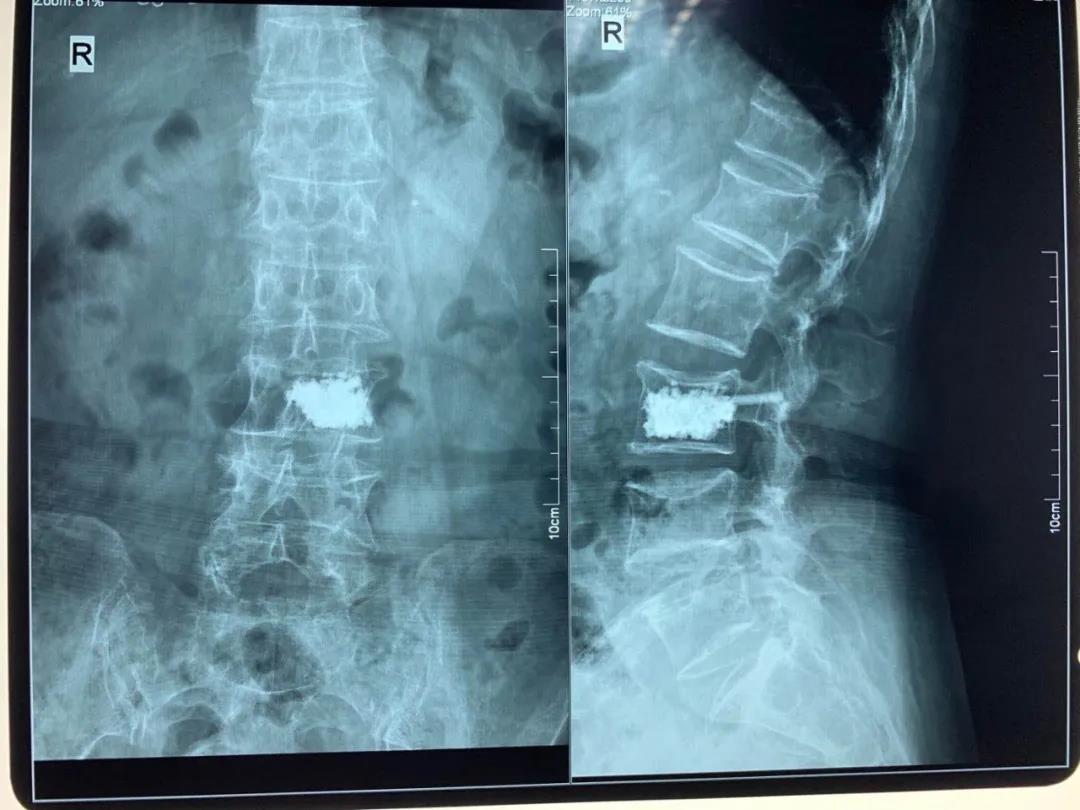

椎體骨折

青壯年椎體骨折無神經(jīng)壓迫癥狀骨二科采用微創(chuàng)經(jīng)皮椎弓根螺釘內(nèi)固定術(shù),避免了手術(shù)大切口引起的椎旁肌破壞,老年骨質(zhì)疏松性椎體壓縮骨折骨二科采用局麻下經(jīng)皮椎體成形術(shù)(PVP、PKP)術(shù),術(shù)后患者即可解除疼痛,第二天恢復(fù)正常生活。

pvp